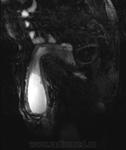

Так..., в виде иллюстрации предъявляю пахово-мошоночную грыжу

Вот прекрасный случай Игоря Ивановича!

Досмотр кишечника через 24 часа после приема пер ос "бария".

Классическая пахово-мошоночная грыжа.